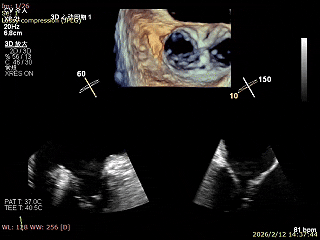

二尖瓣术前评估

复查TTE及TEE检查进一步评估二尖瓣情况。明确为AFMR,二尖瓣功能性反流,2区瓣叶运动,重度FMR(3+),肺静脉逆向血流;2区后叶长度13 mm,2区前叶长度20mm,AP径37mm,瓣口面积4.08cm²,房间隔高度4.5cm,瓣叶无钙化,二尖瓣瓣膜条件适合行TEER手术。

术前Bicom

二尖瓣2区功能性反流

二尖瓣三维视图

2区彩色血流